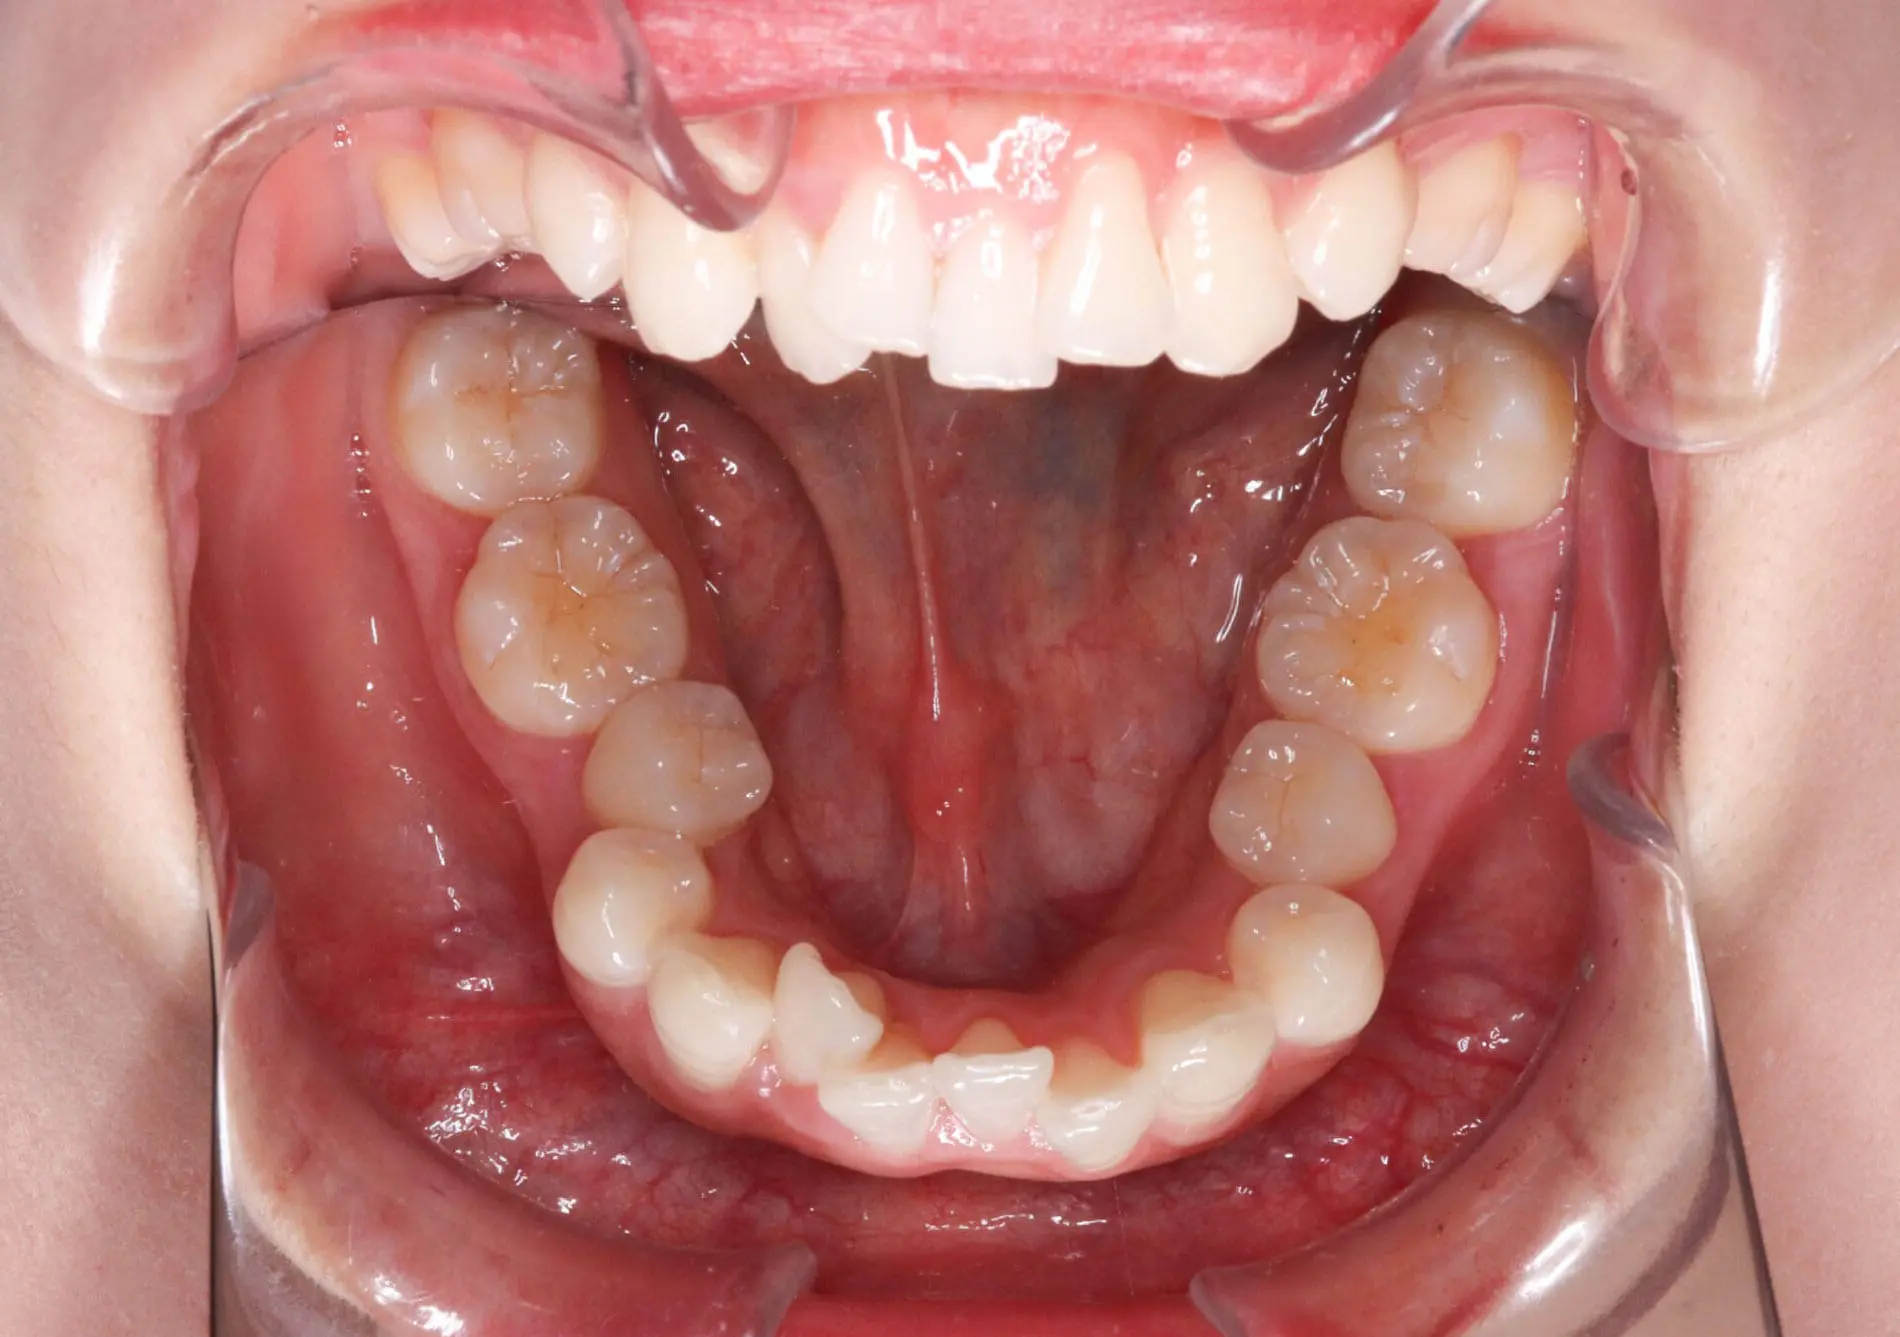

Amazing Braces Before and After Photos in Kirkland, WA

Crowding